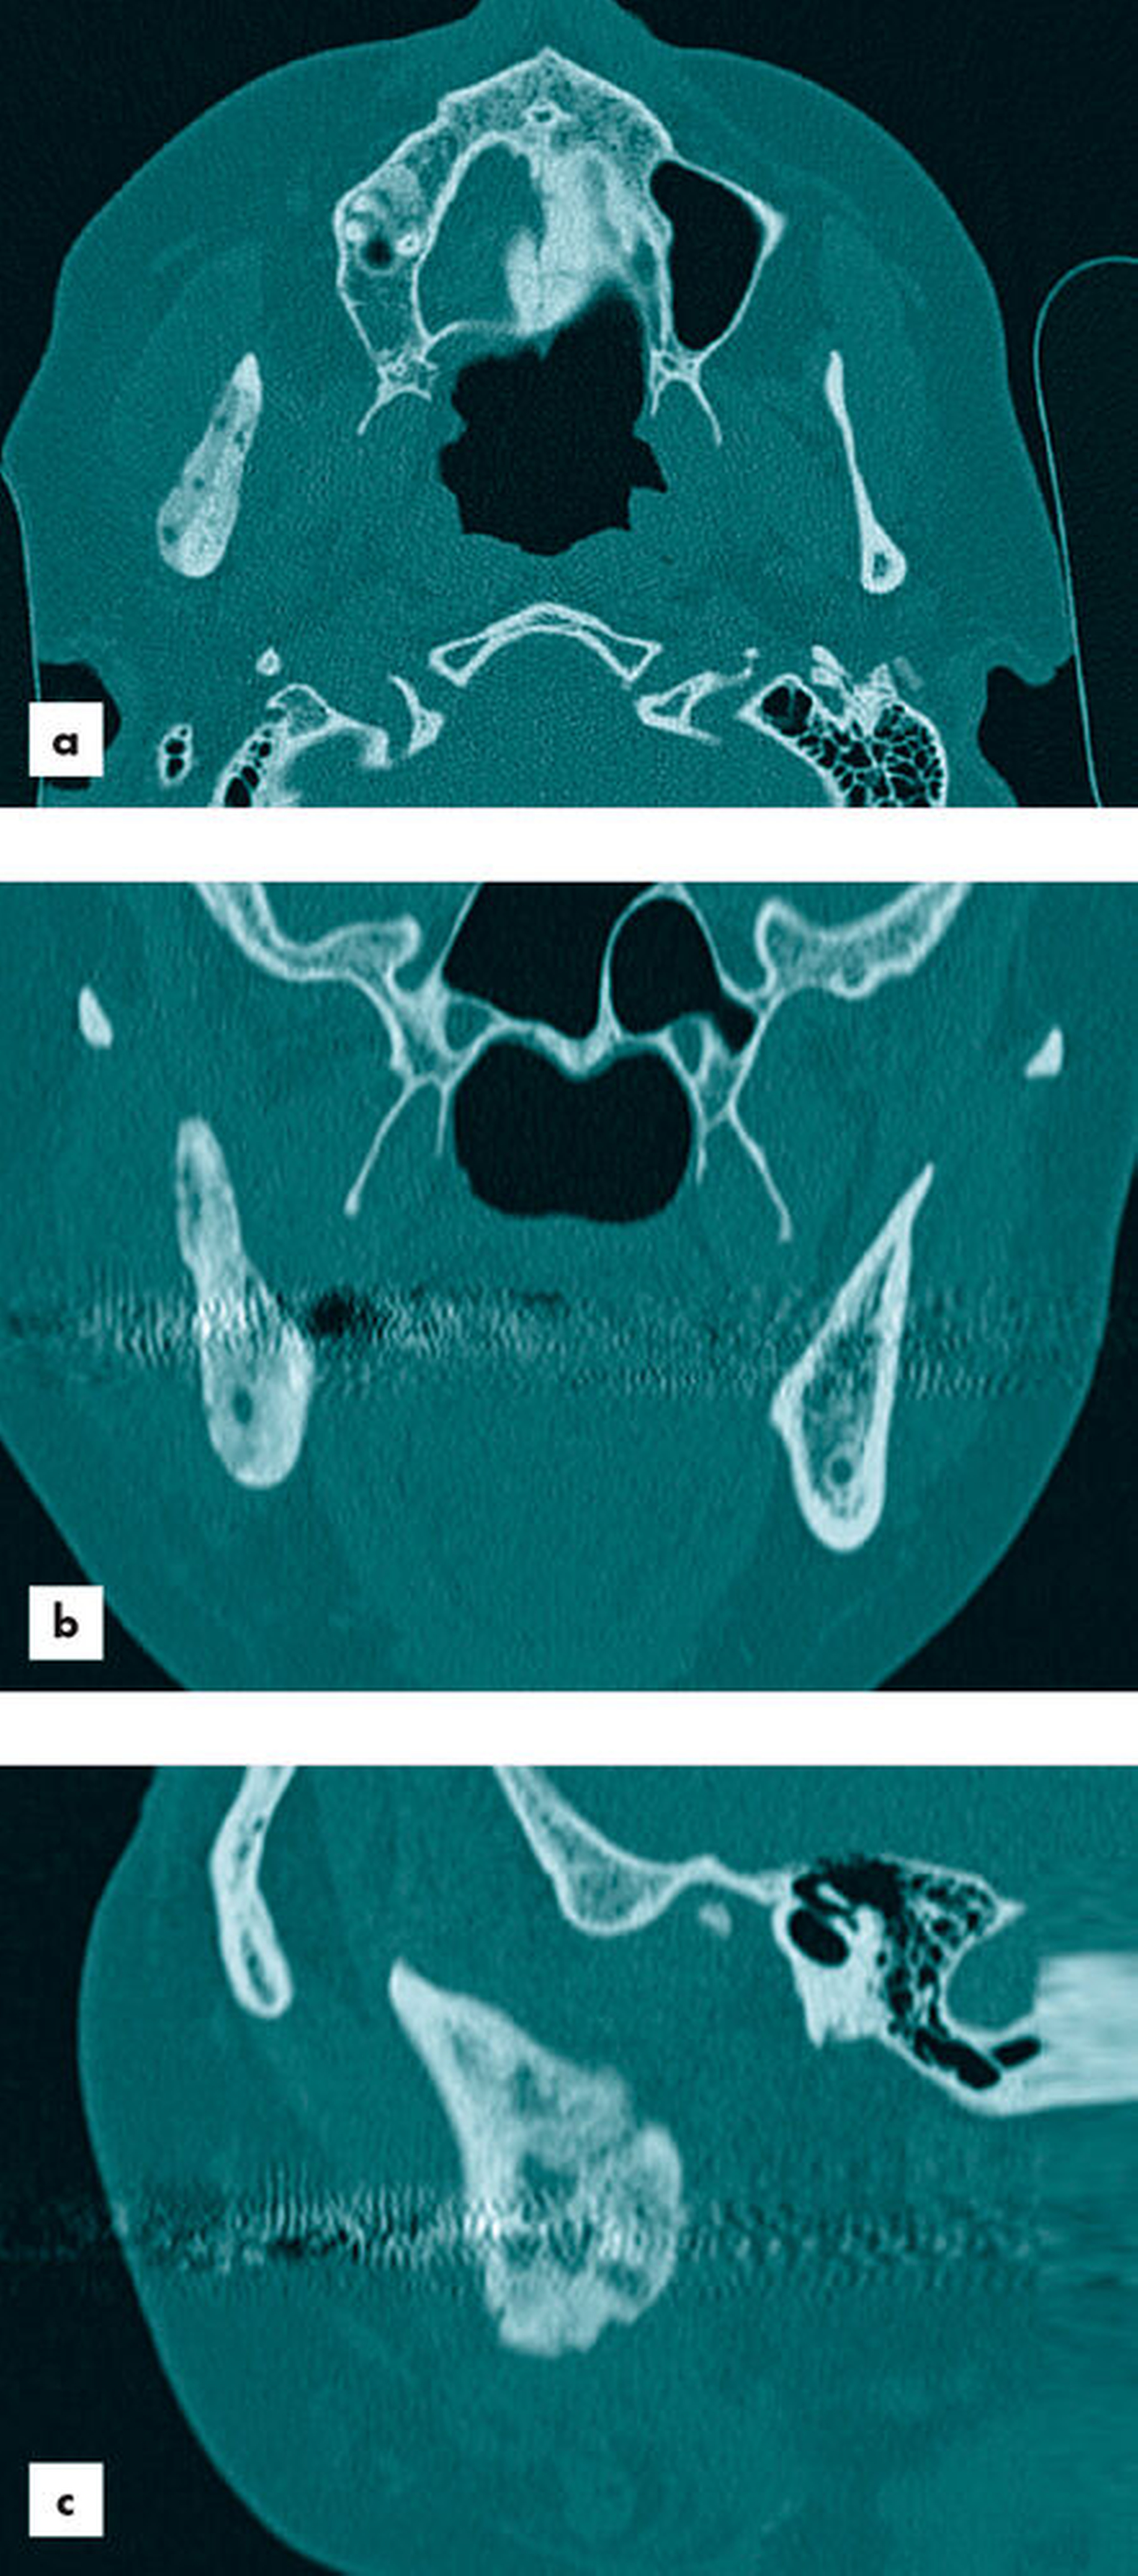

Im Rahmen der Fokussuche erfolgte neben der Anfertigung eines Orthopantomogramms (Abbildung 1) die Durchführung einer Computertomografie (Abbildung 2). Der röntgenologische Befund dokumentierte osteomyelitisch typische CT-morphologische Korrelate wie eine inhomogene großflächige Sklerosierung des rechten Unterkiefers mit zystisch-osteolytischen Veränderungen. Bei klinisch und radiologisch dringendem Verdacht auf eine primär chronische Osteomyelitis des Unterkiefers wurde nach Erörterung der Therapiemöglichkeiten mit der Patientin die Indikation zur zeitnahen operativen Intervention gestellt.